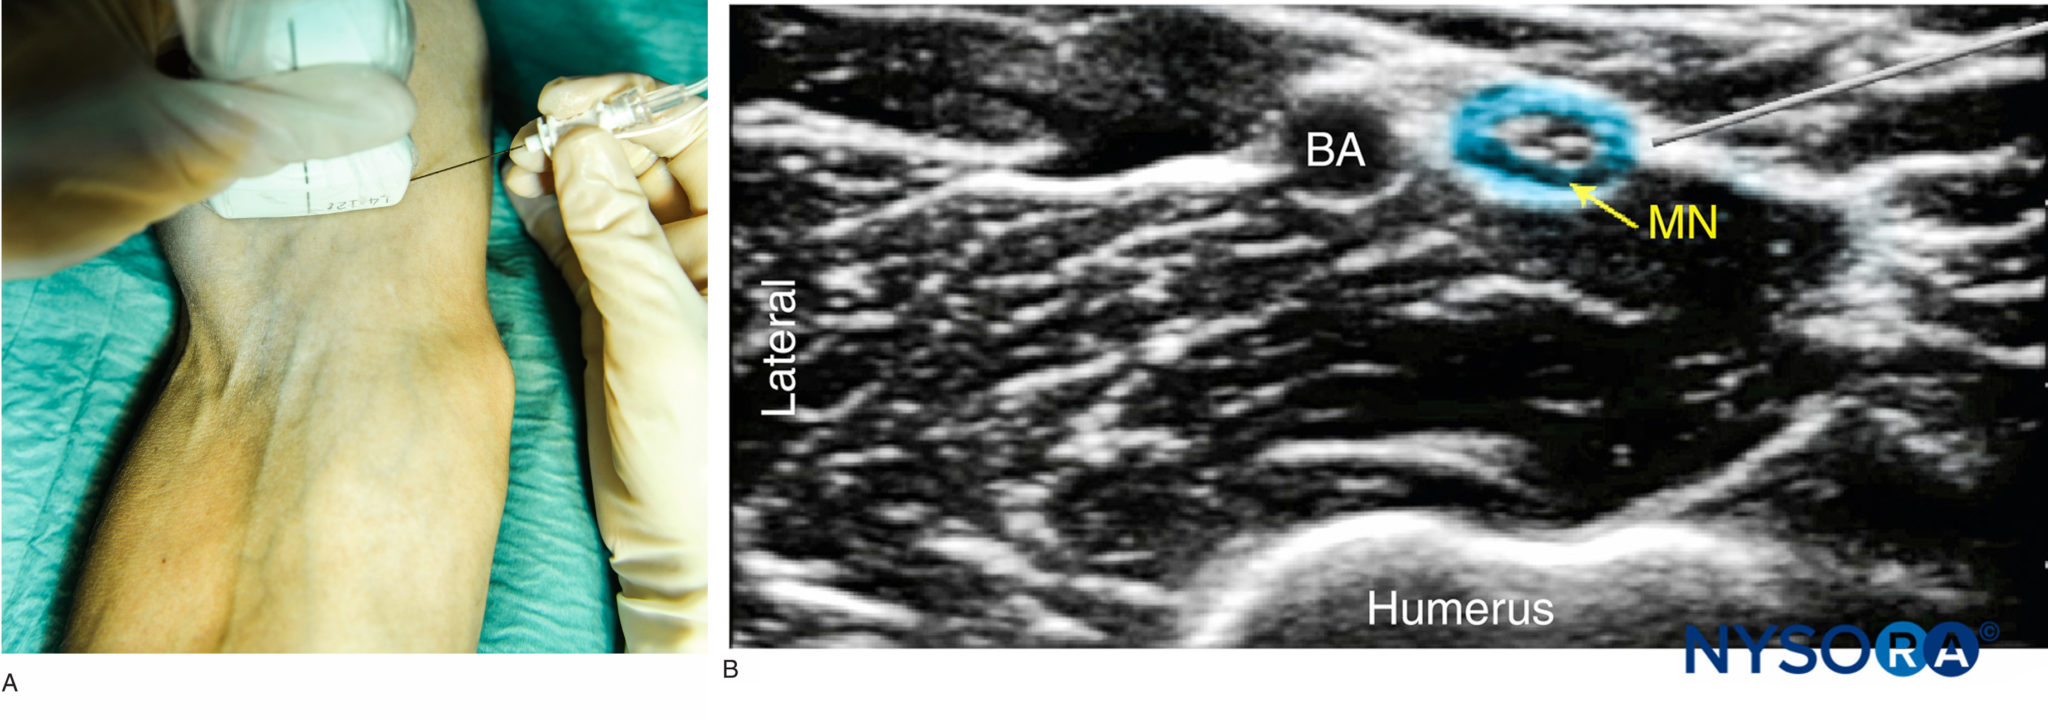

UltrasoundGuided Blocks at the Elbow NYSORA Upper Arm Block Anesthesia It can also help diagnose sources of nerve pain. what is an upper extremity nerve block (shoulder, arm, or wrist hand)? Brachial plexus branches at the. — nerve blocks of the ulnar, median, and radial nerves at the wrist and elbow provide effective anesthesia for a wide range of medical procedures in. — peripheral nerve blocks of. Upper Arm Block Anesthesia.